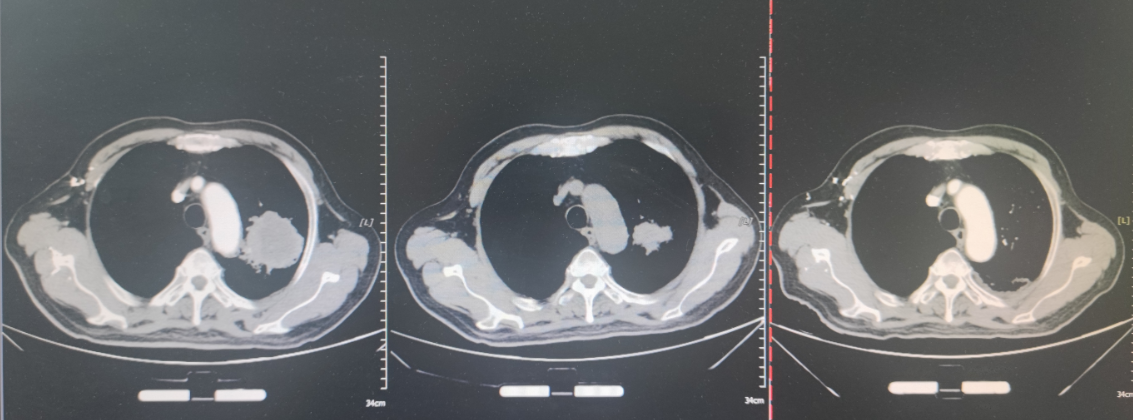

2024-04至2024-08行培美曲塞+卡铂化疗6个周期(具体剂量不详),2024-08开始免疫联合化疗维持治疗,具体方案为培美曲塞+特瑞普利单抗(具体剂量不详),维持治疗直至2025-02-19,期间复查提示病稳定。后患者因自觉腰部疼痛复查。

放疗:2025-5-23起,行Lattice放疗,95%GTV vertex1-6:32Gy/8Gy/4f,95%PTV 50Gy/2Gy/25f,期间给予抗肿瘤、升血、促进食欲、补液,并使用放疗增敏剂甘氨双唑钠增敏。放疗后患者饮食及食欲改善,乏力较前好转。

疗效评估:2025-8-30复查,对比前片,左肺Ca治疗后所见;双侧肾上腺占位,考虑转移;双肺多发小结节,较前相仿;左肺炎性病变;双肺气肿。